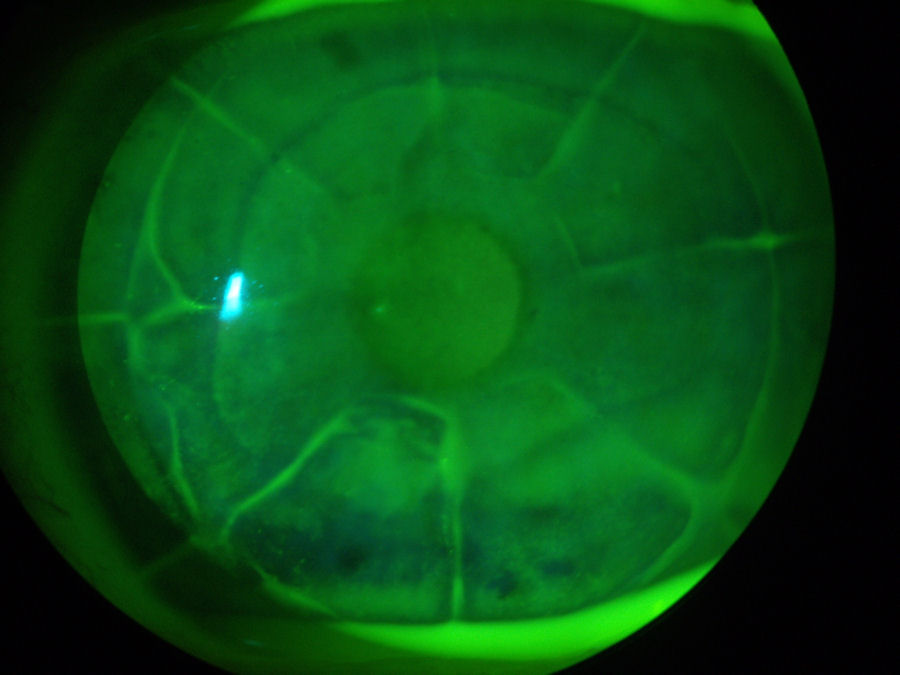

На фотографии ниже представлен глаз пациента, перенесшего операцию LASIK в 2003 году. Край лоскута LASIK все еще виден на этой фотографии 2012 года, демонстрирующей неспособность лоскута к заживлению У пациента есть болезнь сухого глаза , которые проявляются в виде сухих пятен на роговице. (Для освещения поврежденных тканей после закапывания зеленого красителя в глаз используется специальный свет). Небольшие, плохо очерченные овальные или круглые участки чуть ниже лоскута LASIK между 11:00 и 1:00 - это врастание эпителия У пациента также есть эктазия после операции LASIK Нажмите на фотографию, чтобы увеличить ее.